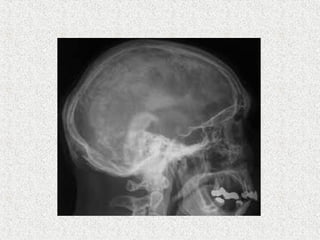

 Skull

 Circumscribed patch of osteoporosis in skull

 Osteoporosis circumscripta

 Cotton wool appearance

 Mixed

 Diploic widening

 Tam o'Shanter sign

 frontal bone enlargement, with the appearance of the

skull falling over the facial bones, like a Tam o'

Shanter hat